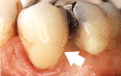

Tandbederf in de kies schemert als een donkere vlek door.

De kies drie jaar na het vullen met composiet.